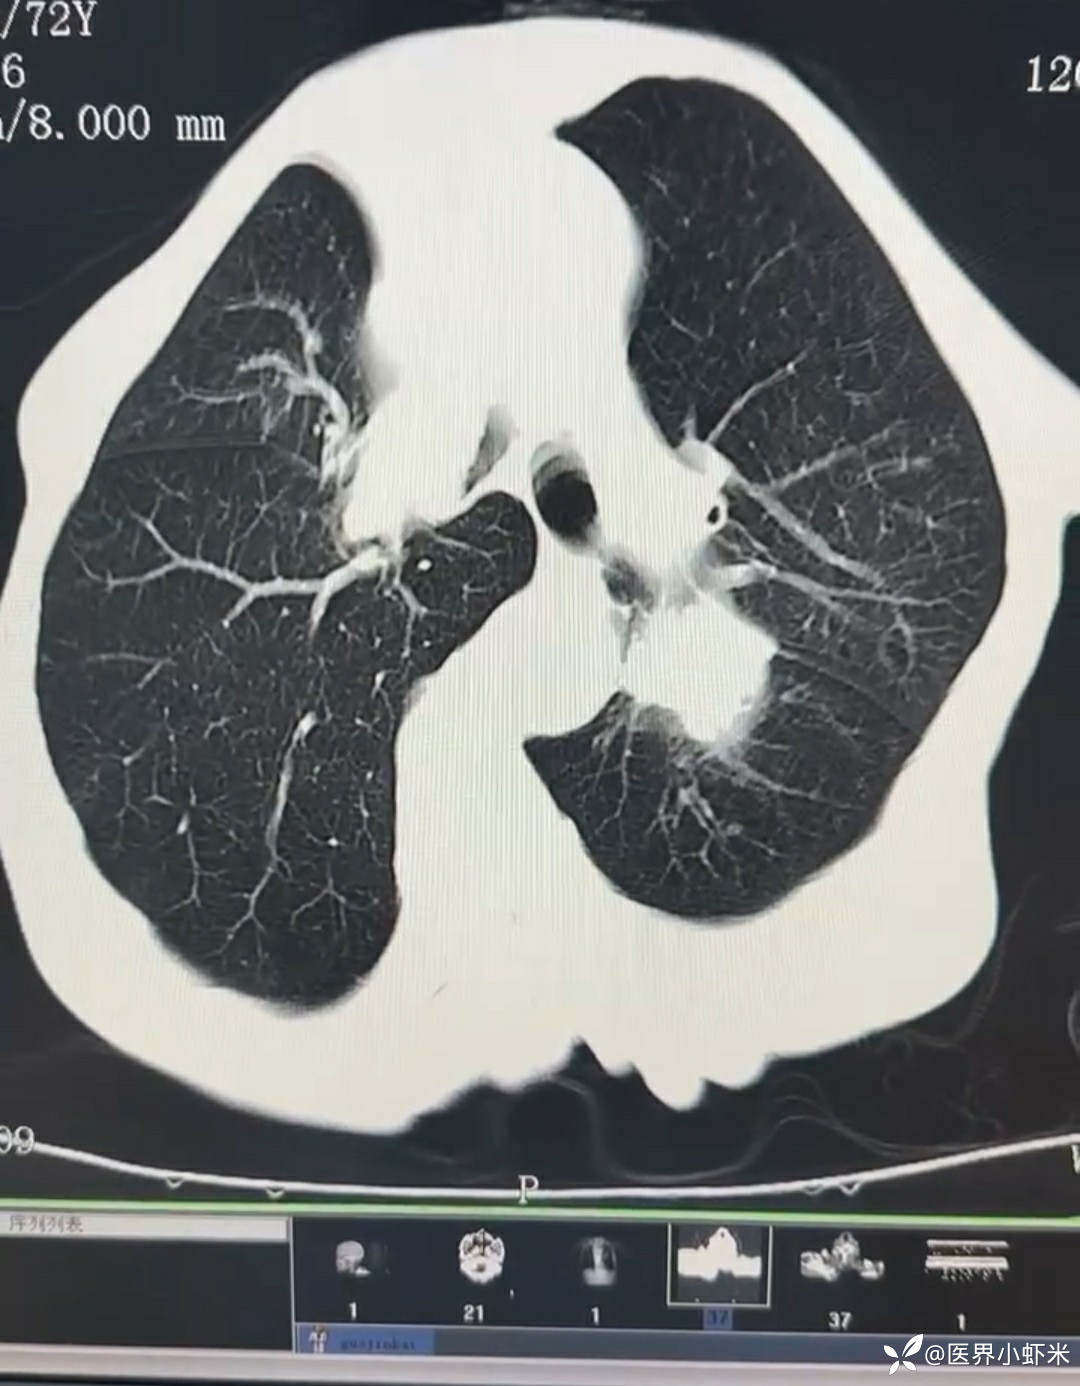

目前考虑:1.中央型肺癌伴2.肝继发恶性肿瘤?2.左丘脑继发恶性肿瘤?3.左丘脑出血?4.肾功能不全5.肝功能异常6右肾萎缩7.肺部感染8.慢性阻塞性肺病7.高血压3级(极高危)。